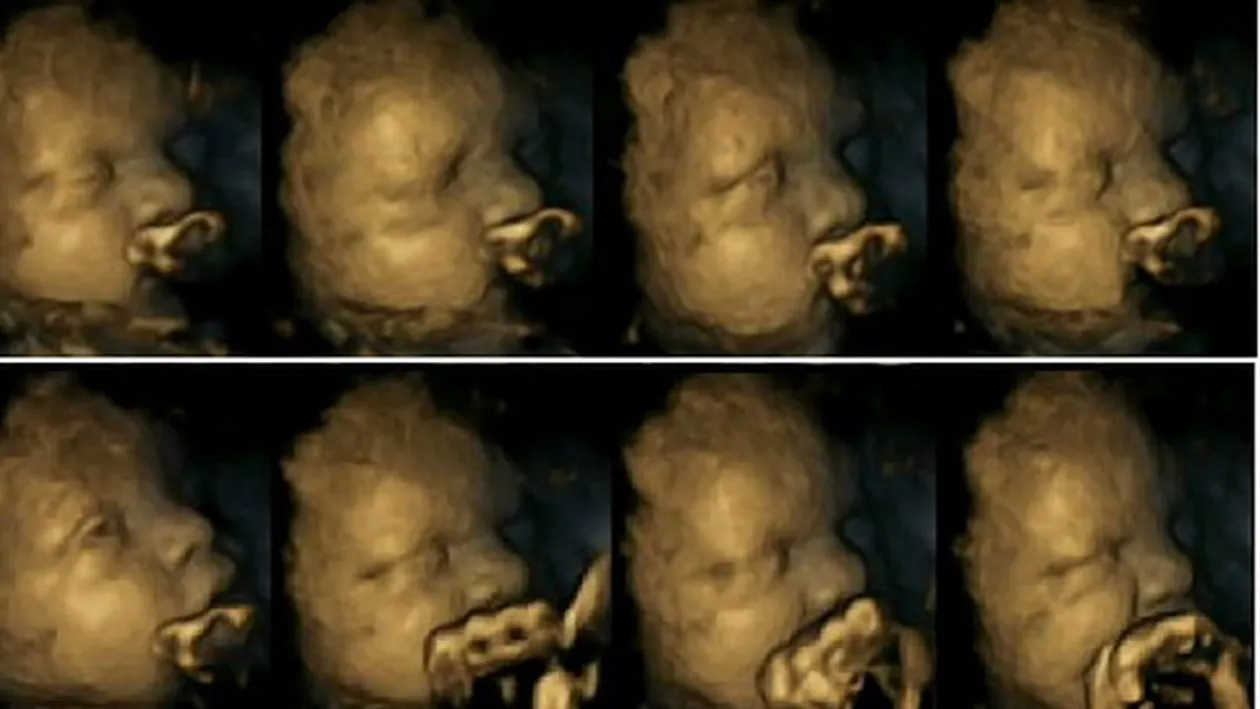

In imaginile de mai sus a fost suprins fatul unei mame care nu fumeaza. In imaginea din interiorul articolului se vede diferenta socanta cu un fat de aproximativ aceeasi varsta dar cu o mama fumatoare.

Rezultatele unui studiu recent arata ca mamele care fumeaza in timpul sarcinii transmit fatului substantele nocive din tigari. Acest lucru il face pe fat sa isi miste gura si sa se atinga de mai multe ori decat copiii nenascuti ai mamelor nefumatoare.

La acest studiu au participa 20 de viitoare mamici. 4 dintre femei fumau cel putin o tigara pe zi. Imaginile surprinse cu o camera 4D arata pana si cele mai mici miscari ale fatului.